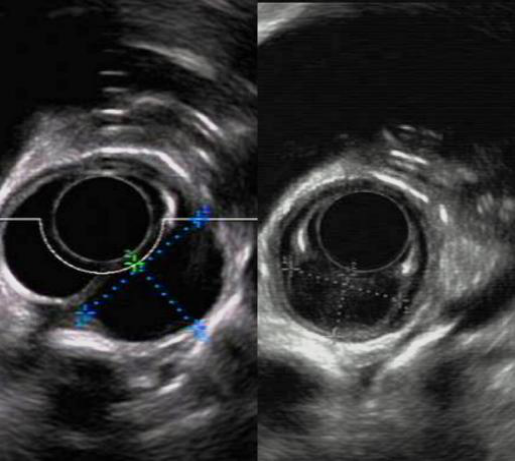

在朋友的推荐下,杨先生来到ac米兰官网中文网站一院,经过腔镜肿瘤外科李军教授,消化内科徐洪雨教授及胸外科姜久仰教授等多学科专家会诊。徐洪雨通过超声内镜检查,提出“可以尝试通过内镜黏膜下隧道技术切除肿瘤,而且可以通过一条隧道切除两个肿物”的手术方案。

内镜下经隧道肿物切除术(STER)创造性地巧妙利用消化道黏膜和固有肌层之间的空间建立“隧道”进行操作,创伤小,术后无体表疤痕,既能充分体现“微创治疗”的优越性,更因术后患者恢复快,住院时间短,治疗费用低,可以大大减轻患者的家庭负担和医保资源。同时,徐洪雨分析患者食管肿物位于食管中上段固有肌层,直径为2.5cm,突向纵膈生长,比邻气管及胸主动脉,术中出现气胸、纵膈气肿、气腹、出血的风险较大,更存在切除第一个肿物后出现气胸而无法切除第二个肿物的后续风险。

徐洪雨和李军联合为患者实施手术。徐洪雨在张蕾护士的配合下在内镜下距患者门齿22cm处建立黏膜下隧道,显露肿物,依次完整剥离两个肿物,切除肿物,关闭隧道入口,食管粘膜完整无破损。术中零出血、无气胸,患者清醒后仅有胸骨后及咽部轻度不适,可自由行动,三天后就可以进流食,目前患者恢复良好,已治愈出院。